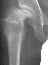

- 2 month Office Follow Up: Rt hip Xray: progressive destruction of capital

femoral epiphysis, cystic changes in metaphysis consistent with AVN.

- Age 6: Valgus osteotomy for subluxation and 2cm leg length inequality.

- Age 15: Valgus osteotomy for hip incongruity.

- Age 20: Hip arthroscopy. Hip fusion recommended.